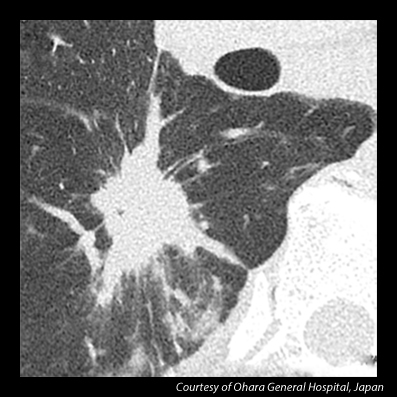

The world's first Ultra-High Resolution CT (UHR CT) capable of resolving anatomy as small as 150 microns, providing CT image quality with resolution typically seen only in cath labs. The UHR detector is newly designed to provide twice the resolution when compared with today’s CT technology, with an all-new detector as well as tube, gantry and reconstruction technologies.

-150 micron, 50 lp/cm* resolution